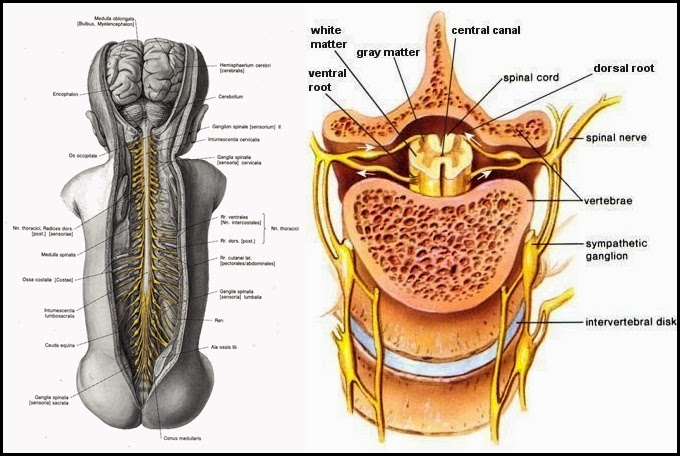

Sistem Saraf Pada Manusia Sistem Saraf Pusat Sistem

Sistem Saraf Pada Manusia Sistem Saraf Pusat Sistem

Struktur Dan Fungsi Sumsum Tulang Belakang Medula Spinalis Weschool Id

Struktur Dan Fungsi Sumsum Tulang Belakang Medula Spinalis Weschool Id

Penyebab Cedera Saraf Tulang Belakang Dan Dampaknya Bagi Tubuh Alodokter

Penyebab Cedera Saraf Tulang Belakang Dan Dampaknya Bagi Tubuh Alodokter

Penyebab Cedera Saraf Tulang Belakang Dan Dampaknya Bagi Tubuh Alodokter

Penyebab Cedera Saraf Tulang Belakang Dan Dampaknya Bagi Tubuh Alodokter

Fungsi Sumsum Tulang Belakang Mekanisme Penghantaran Impuls Pada Tulang Belakang

Fungsi Sumsum Tulang Belakang Mekanisme Penghantaran Impuls Pada Tulang Belakang

Struktur Dan Fungsi Sumsum Tulang Belakang Medula Spinalis Weschool Id

Struktur Dan Fungsi Sumsum Tulang Belakang Medula Spinalis Weschool Id